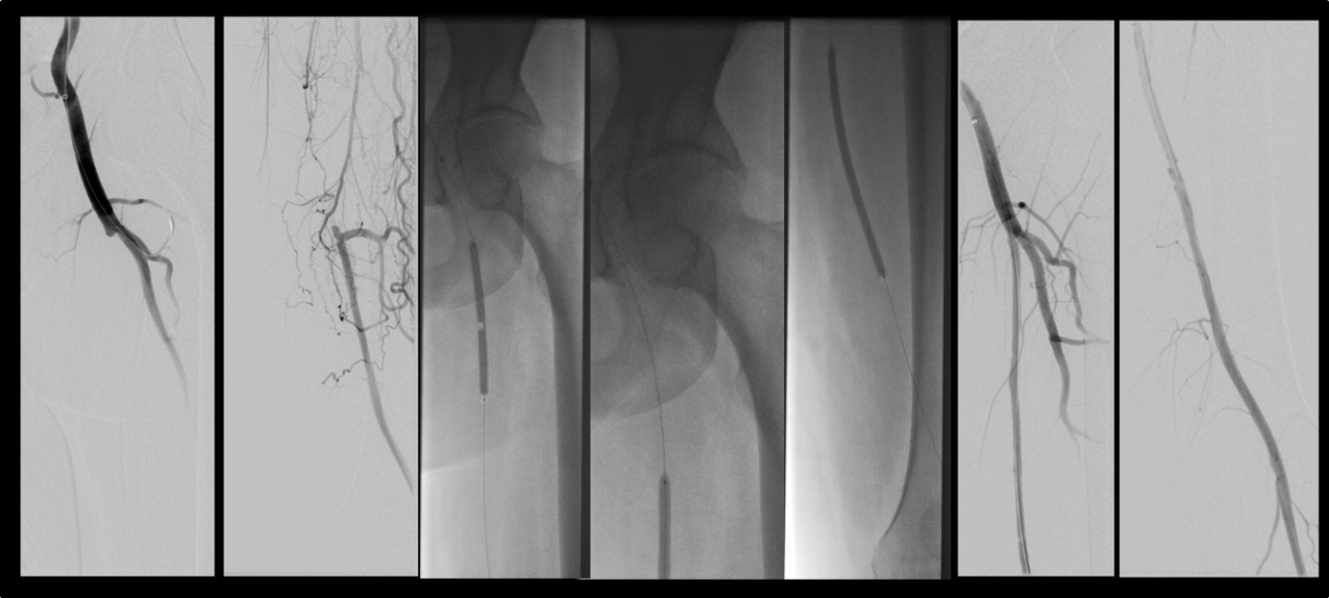

Für die Behandlung der AVK (Arterielle Verschlusskrankheit; Schaufensterkrankheit) gibt es mehrere Methoden, die kombiniert, aber auch als alleinige Therapie angewandt werden können. Die Wahl des geeigneten Verfahrens ist abhängig vom Ausmaß der Beschwerden, vom Alter und dem allgemeinen Gesundheitszustand des Patienten, vom betroffenen Blutgefäß und vom Ausmaß der Veränderungen an den Blutgefäßen. Die Klinik für Diagnostische und Interventionelle Radiologie bietet dabei das komplette Spektrum an minimal-invasiven kathetergestützten Verfahren der modernen Gefäßmedizin zur Wiedereröffnung verengter oder verschlossener Blutgefäße an. Hierzu gehören der Einsatz von Ballons zur Aufweitung von Gefäßen sowie der Einsatz von Stents und Geräten zum Ausschälen von Plaques und Verkalkungen (Atherektomie).

Die Steuerung des Eingriffs läuft dabei unter Zuhilfenahme bildgebender Techniken wie z.B. Röntgendurchleuchtung und Angiographie, in Echtzeit. Mit den kathetergestützten Verfahren können sowohl Becken- und Beingefäße als auch Eingeweideschlagadern behandelt werden (z.B. die Nierenarterien oder die Mesenterialgefäße).